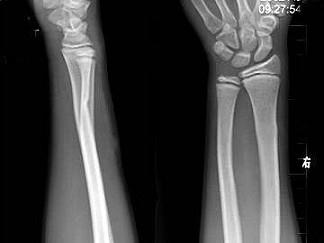

男,10岁,外伤,结合图像,最可能的诊断是?(?)A.未见异常B.骺移骨折C.青枝骨折D.腕关节脱位E.踝关节脱位

问题 男,10岁,外伤,结合图像,最可能的诊断是?(?)

选项 A.未见异常 B.骺移骨折 C.青枝骨折 D.腕关节脱位 E.踝关节脱位

答案 C